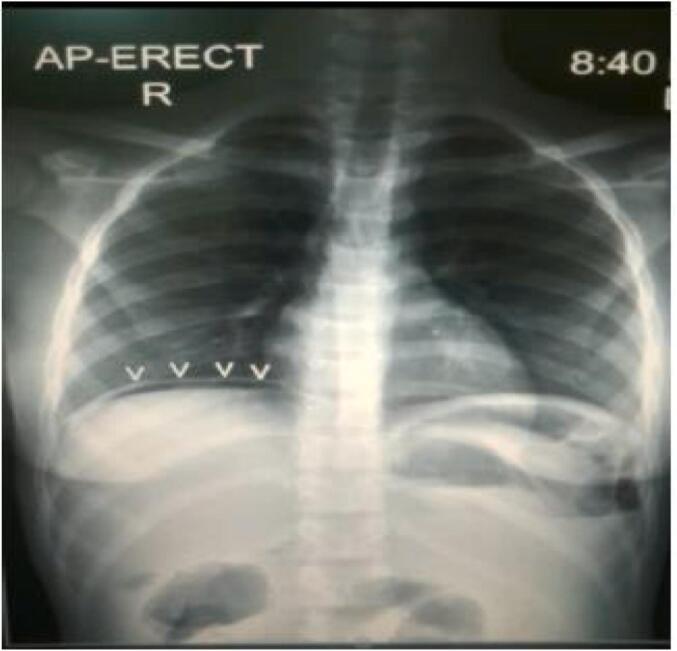

Rectal and pelvic examination was unremarkable. The patient was admitted for resuscitation and further workup. Labs were notable for leukocytosis and a hemoglobin of 6 g/dL, electrolytes, and liver function tests were within normal range. Abdominal ultrasound demonstrated that the inguinal wound was continuous with a loop of ileum incarcerated within the femoral space as well as peri-ileal fluid and a fluid collection in the hepatorenal space. Abdominal X-ray revealed pneumoperitoneum under the right hemidiaphragm (Fig. 2). The patient was diagnosed with peritonitis associated with an EC Fistula. An obstructed Richter's femoral hernia seemed likely to be misdiagnosed and treated as a groin abscess. A pre-operative blood transfusion was done in addition to Intravenous fluids. The patient was consented for exploratory laparotomy which was performed through a midline incision. On opening the abdomen, a distal ileum loop (about 25 cm proximal to ileocecal junction) was found to be incarcerated within the internal femoral ring, which was retrieved back into the abdominal cavity (Fig. 3). There was perforation and ischemia (around 6 cm) over the adhered loop. Resection of the necrotic segment of ileum was done with double barrel ileostomy.

Fig. 2.

Revealed a pneumoperitoneum under the right hemidiaphragm.